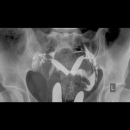

HSG